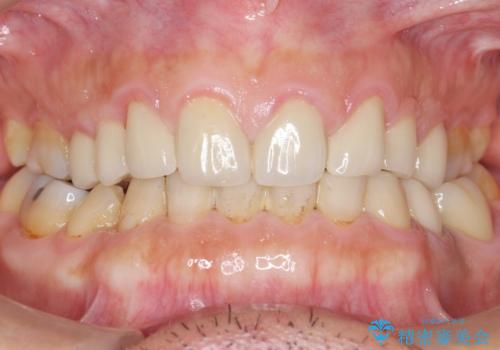

古い被せ物をセラミックにしたい 40代男性

- 奥歯の被せ物をセラミックにしたいとご希望され、来院された患者様です。

左下の奥歯(左下6)の劣化した白い被せ物と金属の土台を除去し、セラミッククラウンによる補綴治療を行いました。

セラミッククラウンの天然歯のような自然な仕上がりと咬み心地に喜んで頂けました。

クラウンの種類:オールセラミッククラウン スタンダード